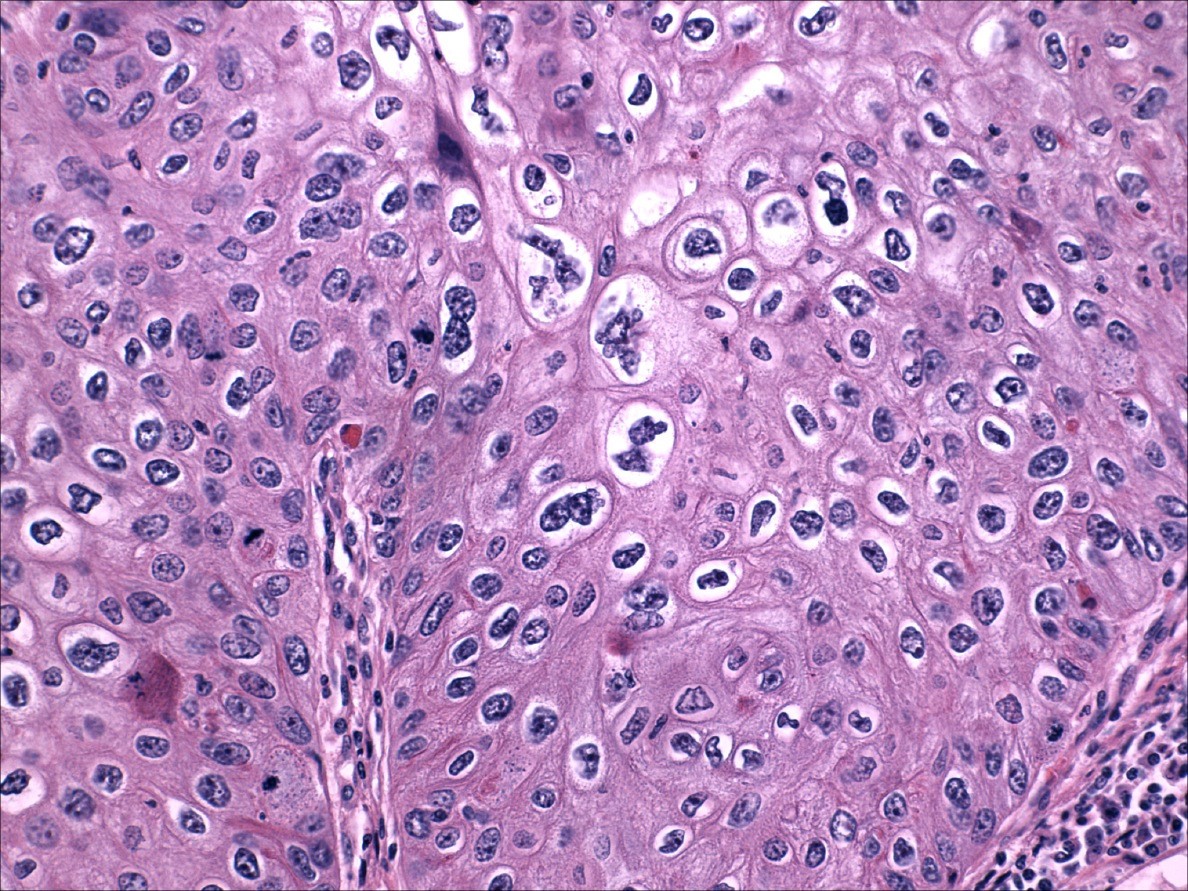

Lowgrade dysplasia in gallbladder epithelium (H& x400). Download Dysplastic Glandular Epithelium This article addresses the spectrum of atypia and dysplasia within the bladder epithelium and the diagnostic categories developed to further. Gastric dysplasia is defined as an unequivocally neoplastic epithelium. Barrett's esophagus (be) is a complication of chronic gastroesophageal reflux and results in the replacement of the normal stratified squamous epithelium of the esophagus. On morphology, the carcinogenetic process of barrett’s. Dysplastic Glandular Epithelium.

High grade dysplasia ofglandular epithelium (H&E). Download Dysplastic Glandular Epithelium Dysplasia, a synonym of intraepithelial neoplasia, is the only marker that can be used at the present time to delineate a population of patients at high risk of cancer. On morphology, the carcinogenetic process of barrett’s mucosa progresses through increasing grades of epithelial dysplasia. Glandular dysplasia (or atypical hyperplasia) has been proposed as a pathologic entity on the basis of. Dysplastic Glandular Epithelium.